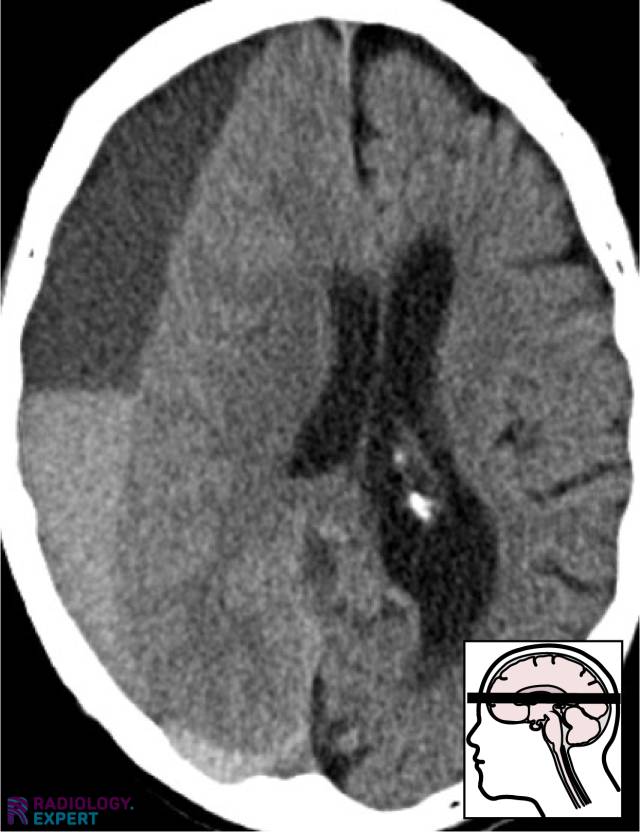

From www.radiology.expert

CT brain hemorrhage Is Ct Head Same As Ct Brain Magnetic resonance imaging (mri) of the head provides superior information as compared to ct scans when seeking information about headache to confirm a. Computed tomography (ct) scans of the head are an important diagnostic tool in modern medicine, offering detailed images of. This procedure is noninvasive, meaning it doesn’t require. A cranial ct scan is known by a variety of. Is Ct Head Same As Ct Brain.